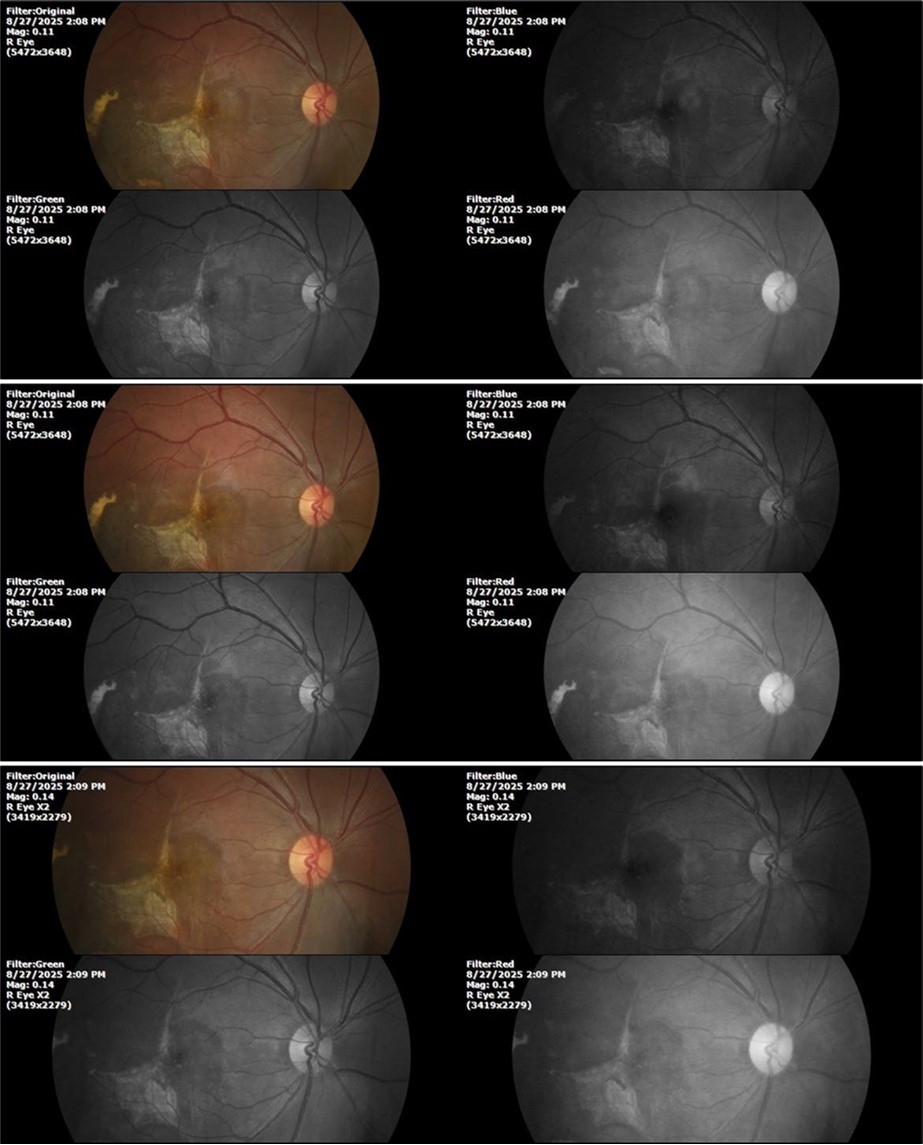

August 26, 2025

It's been fine, there's only a little veil that prevents it from seeing well completely, although it's very transparent (Figure 31, Figure 32, Figure 33, Figure 34, Figure 35, Figure 36).

94 %

62 x ́

++/++

Figure 31.The photograph of the right eye shows an almost normal mirror reflection, as well as a better pupillary dilation.

Figure 32.The macro photograph of the right eye shows us a cornea, anterior camera, and crystalline lens in very good condition.

Figure 33.The 3 previous photographs show that whitish mass has almost completely disappeared, and to date only a remnant remains on the left side of the photograph. The chorioretinal scar that is now observed corresponds to the area affected by the blunt trauma, which presumably caused rupture of Bruch's membrane. Fortunately, the macular region has recovered almost in its entirety, so the impairment in central vision was minimal.

Figure 34.The mirror reflection of the healthy eye (L. E.) continues within normal limits.

Figure 35.The anatomy of the anterior segment of the left eye is shown without alterations.

Figure 36.The retina, optic nerve, choroid, and macula of the left eye do not show any evidence of sympathetic ophthalmia.